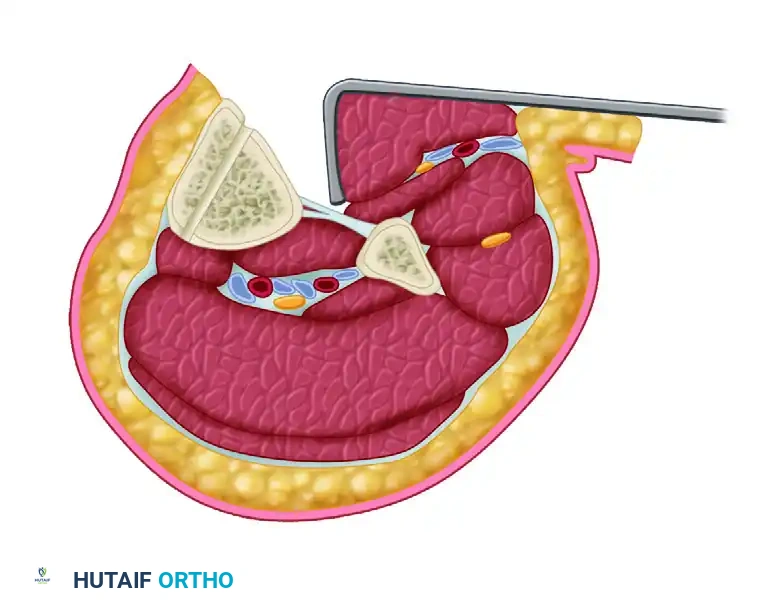

- Anterior Exposure: To expose the osteotomy site, make a longitudinal incision over the anterior compartment, exactly one fingerbreadth lateral to the tibial crest, extending along the proposed longitudinal osteotomy site.

- Extraperiosteal Dissection: Translate the anterior compartment musculature posteriorly. This allows for an extraperiosteal exposure of the lateral aspect of the malunited segment. Only the anterolateral portion of the tibia is exposed. Preserving the medial and posterior periosteum is critical for maintaining the blood supply to the clamshell fragments.

- Transverse Osteotomies: Under strict fluoroscopic guidance, localize the planned positions of the proximal and distal transverse osteotomies. Place a Kirschner wire (K-wire) perpendicular to the anatomical axis to guide the cuts. Use a sagittal saw to create the transverse proximal and distal osteotomies.

Figure D: Surgical exposure for the tibial osteotomy. The anterolateral muscular envelope is retracted posteriorly. Transverse osteotomies are denoted by the planned transverse lines, and the circles represent the drill holes for the longitudinal cut.

- The Clamshell Longitudinal Cut: Create the clamshell component of the osteotomy parallel to the medial tibial face. Begin just posterior to the anterolateral subcutaneous prominence of the tibia and aim in a posteromedial direction.

Figure C: Cross-sectional diagram of the tibial clamshell osteotomy with soft tissues included. The anterolateral muscular sleeve is retracted posteriorly, exposing the lateral aspect of the tibia. The osteotomy is initiated 3 to 5 cm posterior to the anterolateral tibial prominence, angled posteromedially, and parallel to the subcutaneous surface of the tibia.

- Creating Stress Risers: Use a 3.5-mm drill bit to create the path for the longitudinal osteotomy. The goal is to create a bicortical, uniform plane of stress risers.

- Splitting the Cortex: Using the drill holes as a guide, complete the osteotomy of the near cortex with an osteotome.

- Opening the Clamshell: Split the far cortex of the osteotomized segment parallel to the medial face using an osteotome and a laminar spreader. Separate the longitudinal osteotomy of the intercalary segment with the laminar spreader.

- Biomechanical Pearl: The posterior cortex must hinge on the intact periosteal sleeve. If the posteromedial cortex does not open easily, carefully use an osteotome to weaken the posteromedial cortex before reapplying the laminar spreader.